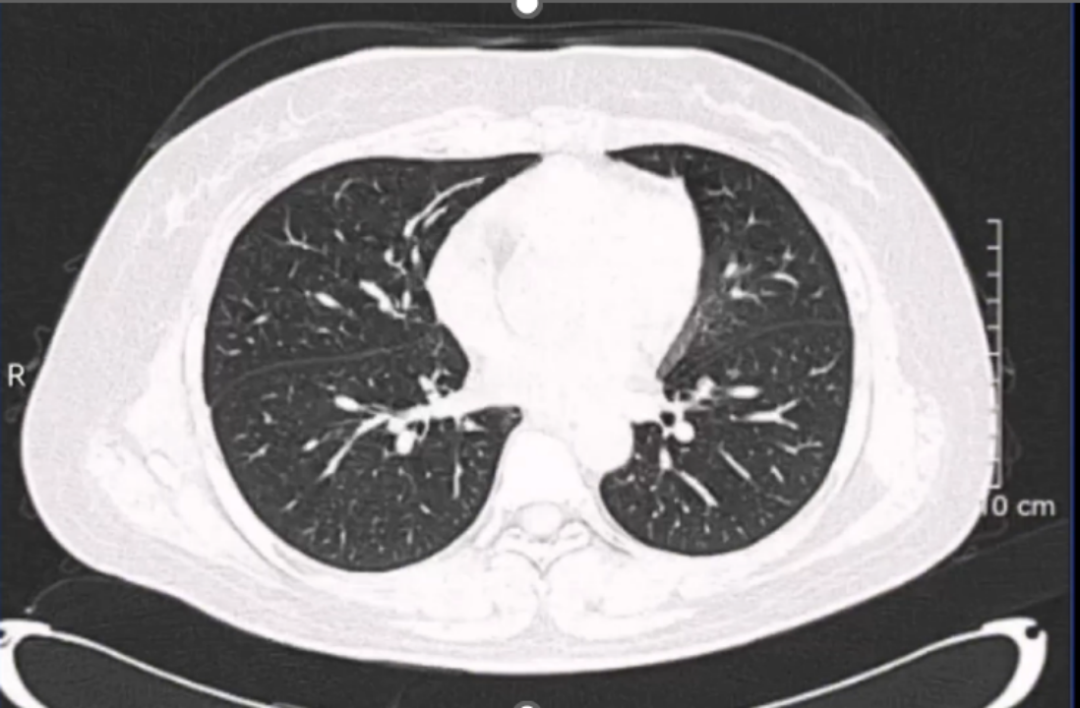

患者女性,34岁,因左肾肿瘤行左肾切除术,术后1年发现局部复发伴肺部转移。患者于2022年6月,因左肾血管平滑肌脂肪瘤在外院接受左肾切除术,2023年7月患者复查发现左侧腹膜后占位,2023-07-21外院超声造影:1.左肾切除术后;2.左侧腹膜后低回声团块,呈“不均匀性增强”(MT可能性大),2023-07-21外院肺部CT:双肺新增多发结节影,考虑转移瘤。2023-07-24在外院行超声引导下左侧腹腔肿物粗针穿刺活检术,病理回报:腹膜后淋巴结送检标本镜下见上皮样血管平滑肌脂肪瘤伴坏死,请结合临床。免疫组化结果: HMB45、MelanA阳性,Desmin少量阳性,CK-pan、CD10、Ihibin-a 阴性。目前诊断:1.左侧腹膜后上皮样血管平滑肌脂肪瘤;2.左肾切除术后。此次会诊的目的:下一步治疗方案?手术?化疗?靶向治疗?

影像科周秀秀主治医师:患者腹部CT影像显示:左侧腹膜后血管平滑肌脂肪瘤,肿瘤体积较大,直径达10cm以上,病灶中央可见坏死灶,同时肺部CT显示双肺新增多发结节影,考虑为转移瘤,提示该肿瘤进展较快,结合病理报告,考虑属于特殊类型的血管平滑肌脂肪瘤。

肿瘤科柳珂副教授:患者肾脏EAML肿瘤术后复发,同时发现肺部转移可能,目前建议的治疗方案是手术切除病灶以达到减瘤目的,同时可以降低肿瘤破裂出血风险对患者造成的生命威胁。该疾病属于结节性硬化病的一种,药物治疗方案推荐包括依维莫司在内的mTOR抑制剂。针对患者双肺新增多发结节影,可考虑行穿刺活检,通过病理会诊加以明确诊断,必要时可进行基因检测,有助于提供更多治疗靶点。同时该病具有遗传倾向,建议患者的直系亲属同时接受TSC基因筛查,有利于早期诊治。